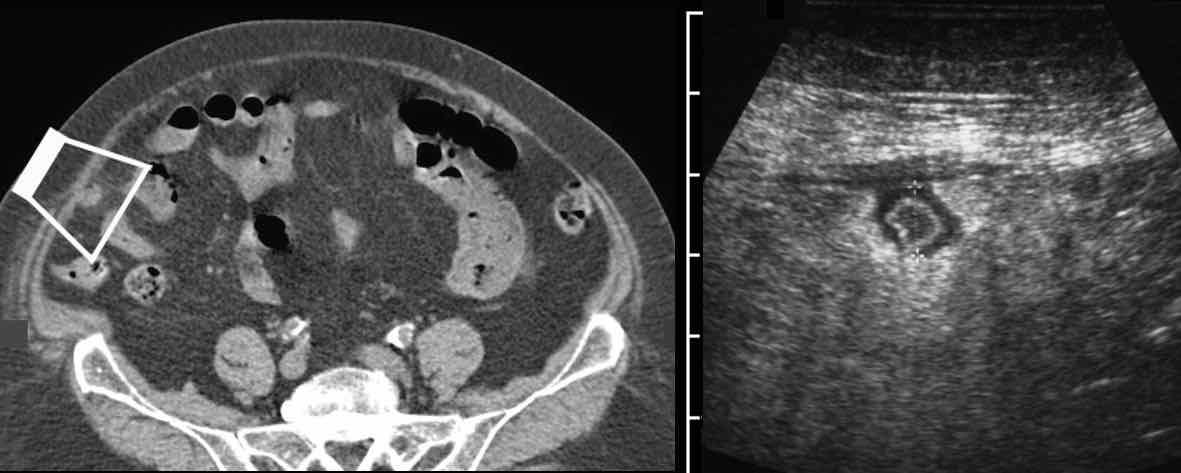

Ở bệnh nhân 16 tuổi này với đau hố chậu phải, các hạch bạch huyết mạc treo to được bao quanh bởi một ít mỡ đang viêm (*) là dấu hiệu siêu âm duy nhất và không xác định được ruột thừa.

CT xác nhận các hạch to (đầu mũi tên), nhưng phát hiện thêm ruột thừa đang viêm (mũi tên), xuất phát từ manh tràng ở vị trí sâu trong tiểu khung.

Bệnh nhân trẻ bị viêm ruột thừa cấp thường có hạch bạch huyết mạc treo to thứ phát.